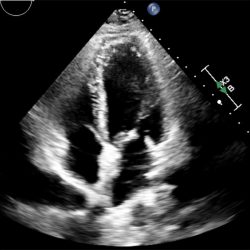

According to the American Society of Echocardiography, cardiac sonographers — also called echocardiographers — are specialists who create detailed images of a patient’s heart using non-invasive, radiation-free ultrasound equipment. The images provide detailed information about the heart’s structure, function and blood flow, which can help physicians diagnose and monitor heart conditions.

Echocardiography can diagnose conditions such as heart murmurs, valve disease and heart failure, can monitor the effectiveness of heart treatments and help assess the severity of damage following a heart attack.